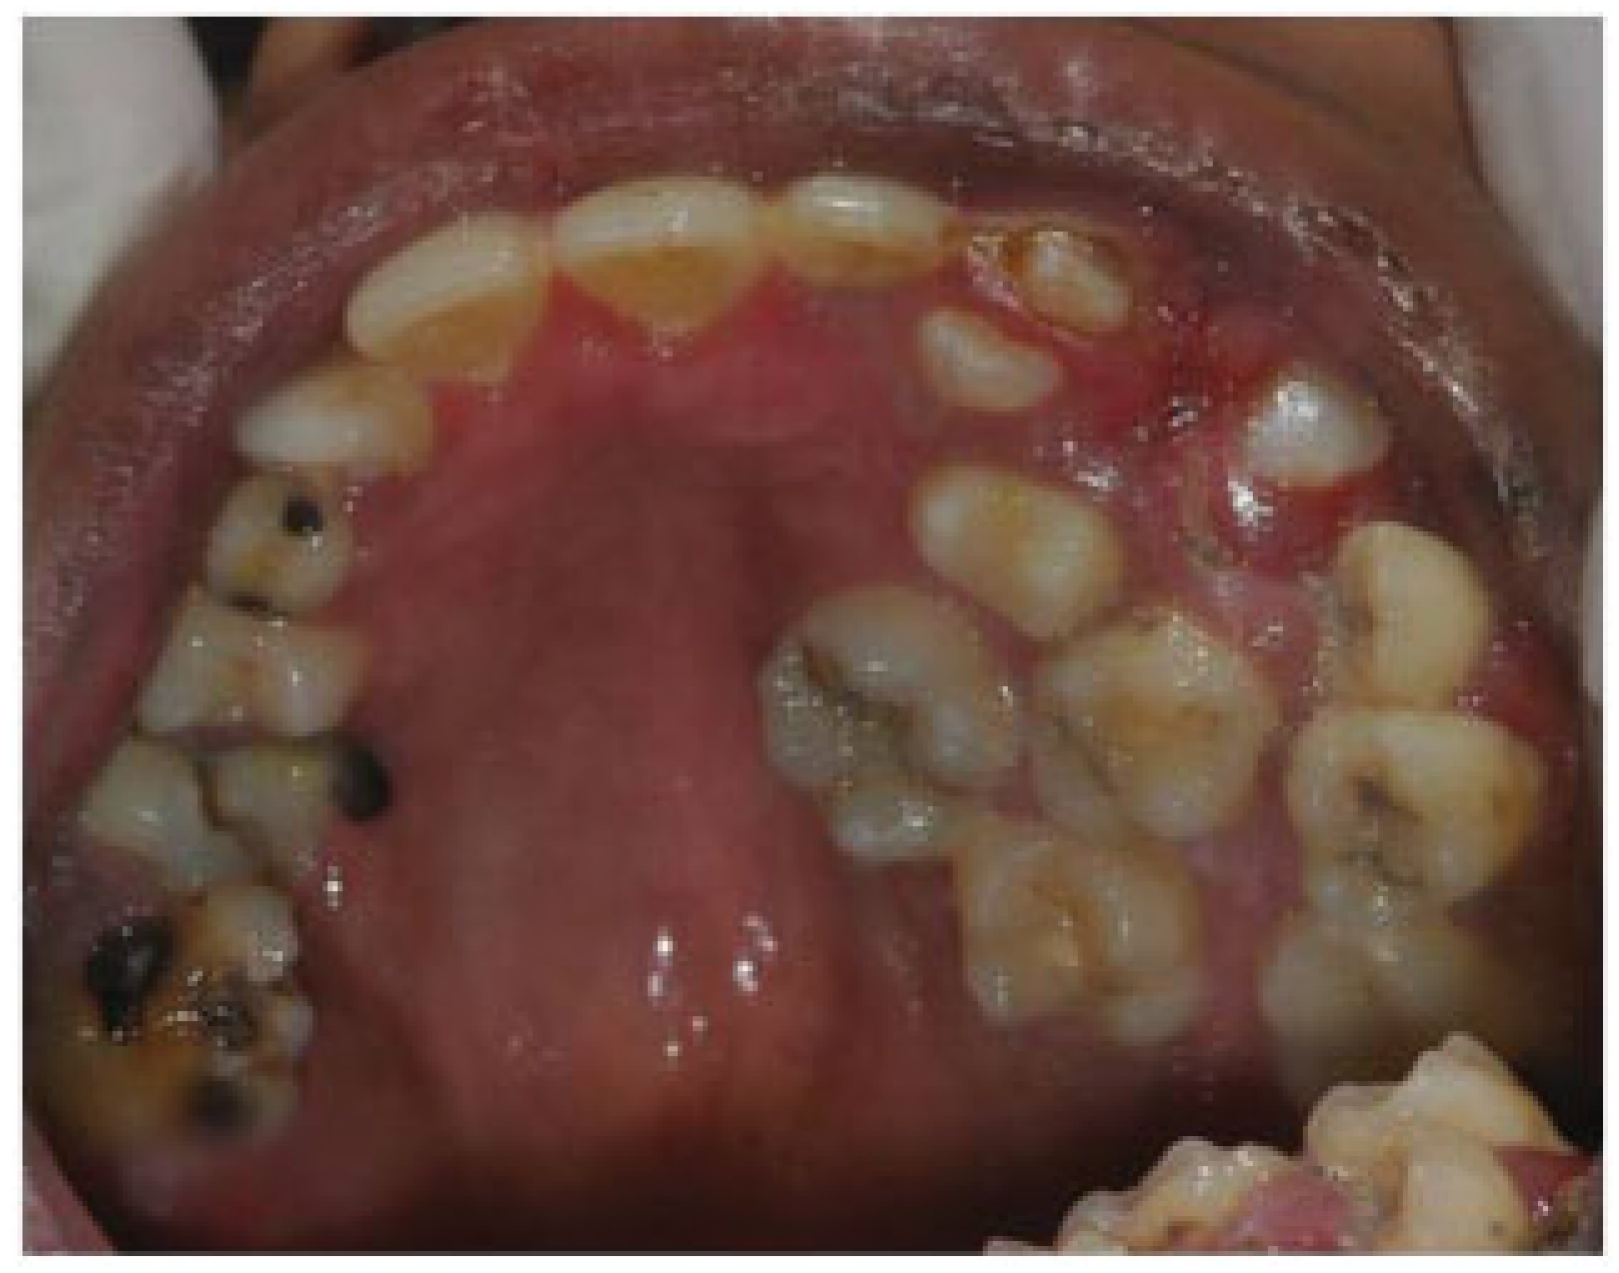

A Rare Case of Multiple Oblique Facial Clefts with Supernumerary Teeth: Case Report

- Incomplete Tessier 7 soft tissue facial cleft and a complete skeletal Tessier 7 cleft on the right side

- Incomplete Tessier 5 skeletal and soft tissue Tessier 6 facial cleft on the left side